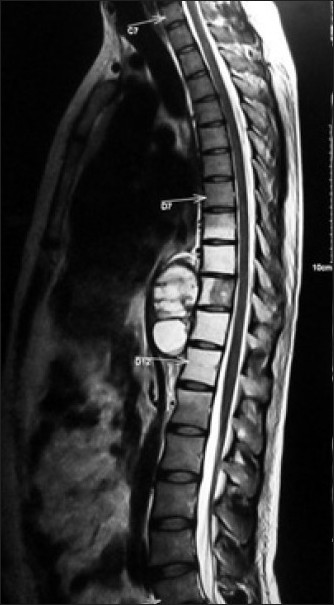

脊髓( spinal cord )是神經系統中重要的一部分。在顱頸的交會處,脊髓向上承接腦幹後,便被嚴密的保護在脊椎的神經腔中,由頸部一直延申到腰椎;右圖即是脊髓在脊椎內分佈情形。

並且在每一節的脊椎孔,脊髓都會分派出一對脊椎神經與軀幹或肢體相連,把軀幹四肢的感覺訊號上傳至大腦的神經中樞,同時也將中樞神經所下達的指令傳達至四肢軀幹。一但脊髓受損,如果損傷的部位在第 5 節頸椎以上,病人將因呼吸衰竭而死亡。如果損傷的部位在第 5 、 6 、 7 節頸椎,將會造成病人四肢癱瘓。胸椎以下的脊髓損傷,也將造成病人下肢麻木癱瘓、大小便失控。